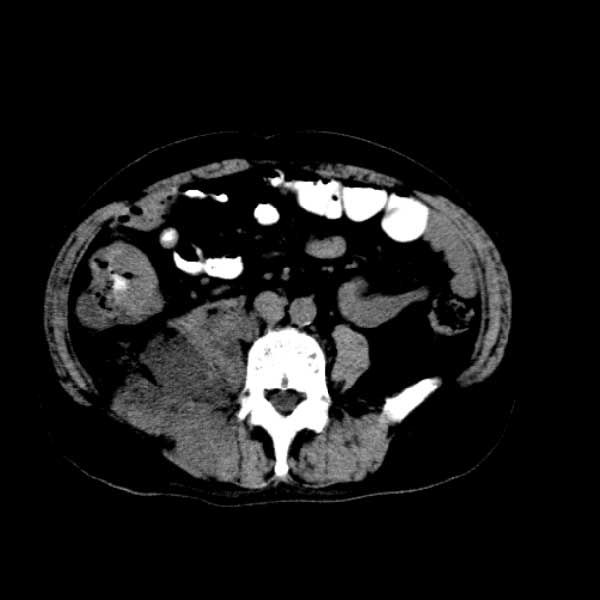

标题: CT13513:男 71 腹部疼痛20余天,近几天高热就诊,骨窗未见异 [打印本页]

标题: CT13513:男 71 腹部疼痛20余天,近几天高热就诊,骨窗未见异

考虑感染性病变可能性大,起源于阑尾?

感染,脓肿形成

考虑为化脓性阑尾炎.脓肿形成.及多肌肉累及.

考虑右侧腰大肌脓肿,向右髂窝、右腹股沟流注。

支持化脓性阑尾炎伴右髂窝脓肿、腰大肌腰方肌脓肿形成。

考虑腹腔及盆腔化脓性炎症,累及右侧髋关节及腹股沟区.

首先考虑化脓性阑尾炎伴腰大肌、腰方肌脓肿,不除外回盲部结核。

回盲部癌待排除。

患者肠镜检查考虑结肠癌,病理证实

患者肠镜检查考虑结肠癌,病理证实。肺部ct可见多发结节,考虑转移